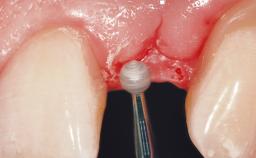

Immediate Flapless Placement of an Implant in a Maxillary Left Central Incisor Site

A 29-year-old female patient presented for treatment to replace the upper left central incisor tooth with an implant- supported restoration. The tooth had been intermittently symptomatic for the previous 12 months. The tooth had originally suffered trauma about 15 years previously. Several endodontic treatments had been performed, including an apicectomy procedure to retain the tooth. The patient was healthy and a non-smoker. She had reasonable expectations in regard to esthetic outcomes and the risk of marginal tissue recession following treatment. At medium smile, the gingival margins of the upper teeth were visible, with a display of 3 to 4 mm of the gingival margins. Gingival recession of tooth 21 and a discrepancy in the gingival levels between teeth 11 and 21 was observable during normal speech and smile.

| Placement Protocol | Immediate implant placement |

| Tooth Site | Maxillary incisor or canine |

| Socket Morphology | Single-root socket |